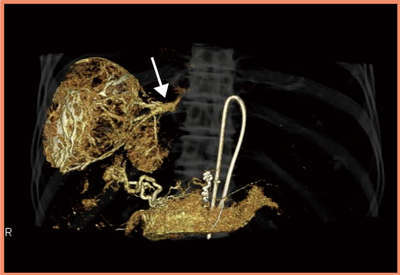

大腸がんの肝転移症例(図3)では,3D-CTAにおいて背側の結節まで濃染され,薬剤の肝内分布も良好に見えたものが,4D-CTAにおいて背側の結節に向かう血管内で血流が押し戻されている様子が確認できた。リザーバーからの抗癌剤注入は,CT撮影時の造影剤の圧入と異なり,スローインフュージョンとなるが,このような状況下では十分な薬剤分布が得られていないと考えられた。実際に,背側部では治療効果が得られず,ADCTの4D撮影によるフローチェックによって,薬剤効果の判定が可能になると考えられる。

図3 4D-CTによる大腸がん肝転移症例の動注リザ―バー療法での

フローチェック

背側側に向かう血管の血流が押し戻されている様子が描出された(→)。